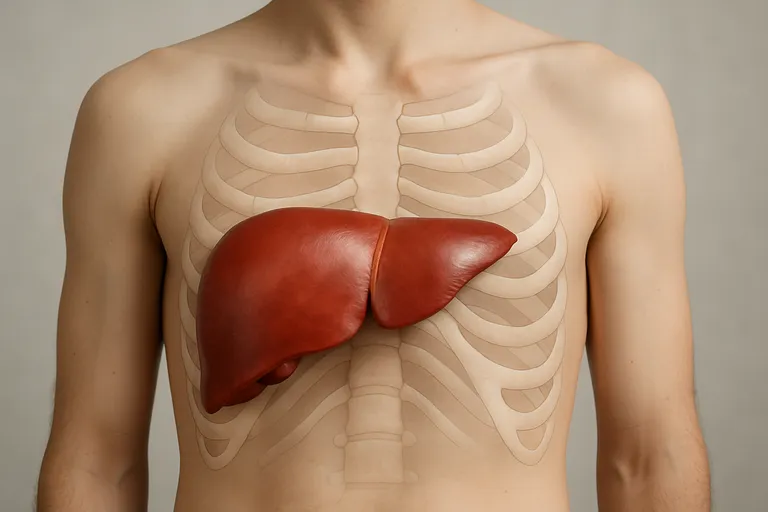

Waar zit je lever precies?

Je lever ligt rechtsboven in je buik, direct onder de rechterribben en tegen het middenrif aan. Het grootste deel bevindt zich aan de rechterkant, maar een dunne linkerkwab steekt over de middellijn naar links, tot net achter je borstbeen. De bovenkant volgt de koepel van het middenrif en beweegt mee met elke ademhaling; bij een diepe inademing zakt de lever 2 à 3 centimeter, waardoor de onderrand net onder de ribben voelbaar kan worden. Het is een groot, stevig orgaan van ongeveer anderhalve kilo dat veel ruimte inneemt in de rechterbovenbuik. Aan de onderkant ligt je galblaas tegen de rechterleverkwab; links ervan liggen je maag en iets lager je darmen, terwijl achter de lever de rechternier en grote bloedvaten lopen.

Dankzij de ribben is de lever goed beschermd en kun je hem normaal gesproken niet zien of voelen. Wil je de plek globaal vinden, leg dan je hand plat onder je rechterribbenboog; daar, iets richting het midden, zit de onderrand. Bij kinderen en slanke volwassenen is die rand soms iets makkelijker te voelen. Houd er rekening mee dat houding, lichaamstype, zwangerschap en een volle maag de positie een beetje kunnen laten variëren, maar je lever blijft hoofdzakelijk rechts. Alleen in zeldzame gevallen, zoals bij situs inversus (een omgekeerde orgaanligging), zit je lever links.

Ligging en begrenzing: rechterbovenbuik en een stukje over de middellijn

Je lever ligt hoofdzakelijk in je rechterbovenbuik, direct onder de rechterribben en tegen het middenrif. De grootste massa zit rechts, maar de linkerkwab steekt als een platte tong over de middellijn naar links, tot net achter je borstbeen. Boven grenst de lever aan het middenrif en de onderrand volgt de ribbenboog; bij diep inademen kan die onderrand heel even onder de ribben voelbaar zijn.

Aan de voorkant zit een bindweefselband die de lever aan je buikwand verankert rond de middellijn, wat de scheiding tussen rechts en links markeert. Achter de lever lopen grote bloedvaten en ligt de rechternier, links ervan zitten je maag en hoger je slokdarm. Door de ribben is je lever goed beschermd, waardoor je hem normaal niet ziet of voelt.